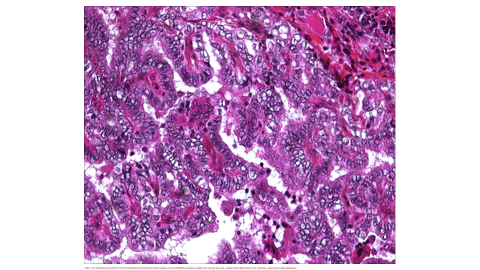

The association between differentiated thyroid cancer and exposure to ionizing radiation has been well-known since the radioactive fallout of the 20th century [1]. Follow-up consultations after radiotherapy must address three major objectives: the assessment of oncological response, the evaluation of acute or late toxicity to ionizing radiation, and the screening for a second cancer [2]. Surveillance is especially indicated for cases with external irradiation such as patients with a history of cervical, upper mediastinal, craniospinal, or total body radiotherapy, in addition to internal contamination exposures due to nuclear accidents. This risk is limited to the development of differentiated thyroid cancer, namely papillary or follicular types [2]. In fact, the risk is highest for irradiation received before the age of five and decreases with age, becoming non-significant if irradiation takes place after 15 to 20 years of age [3].We report a case of radiation-induced papillary thyroid carcinoma in a 16-year-old adolescent, managed in the Nuclear Medicine Department at Hassan II-Fez University Hospital Center.